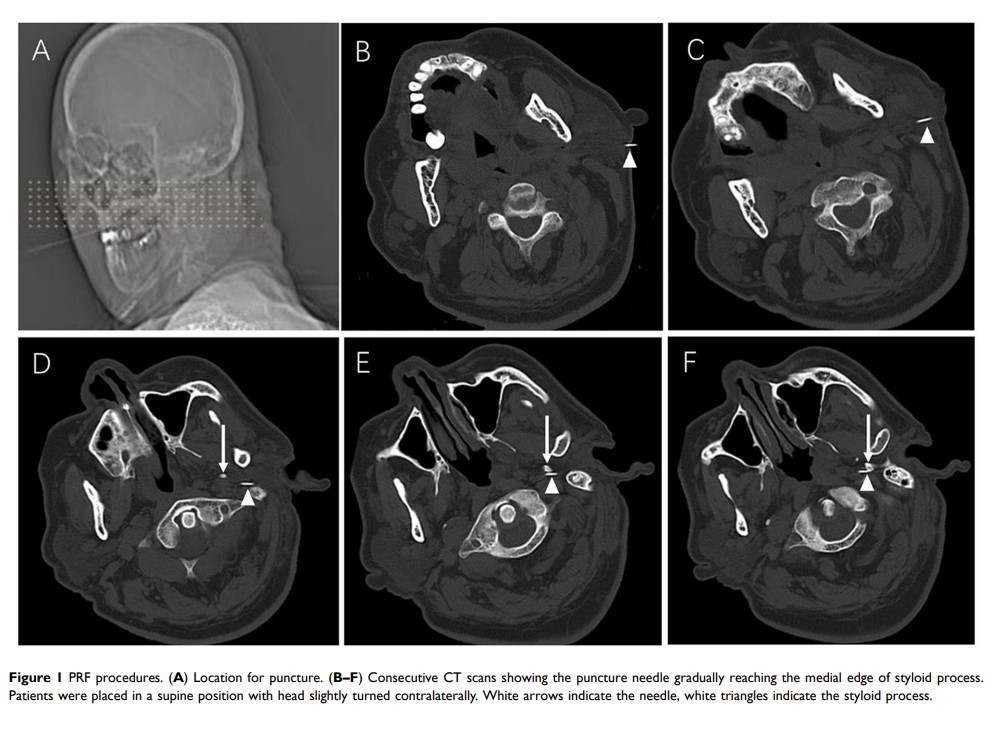

CT 引导的脉冲射频术治疗特发性舌咽神经痛的长期疗效:多中心病例系列回顾